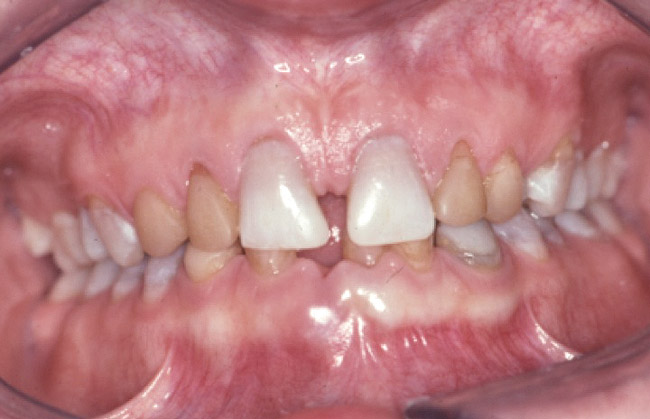

Loss of vertical dimension can be assessed through patient examination intraorally, extraorally, and functionally. Missing teeth and/or teeth worn from clenching or bruxing are the most common intraoral signs of a decreased VDO. Congenitally missing teeth can result in loss of vertical dimension with possible implications of compromised comfort, speech, and chewing (Figure 6 through Figure 8).

Figure 6. The patient is congenitally missing the maxillary lateral incisors and canines and all lower incisors and canines, causing concerns about esthetics. The maxillary laterals and canines and mandibular canines have been bonded with composite.

Figure 6

Figure 7. The mandibular incisors are loose, and No. 25 has recently been lost.

Figure 7